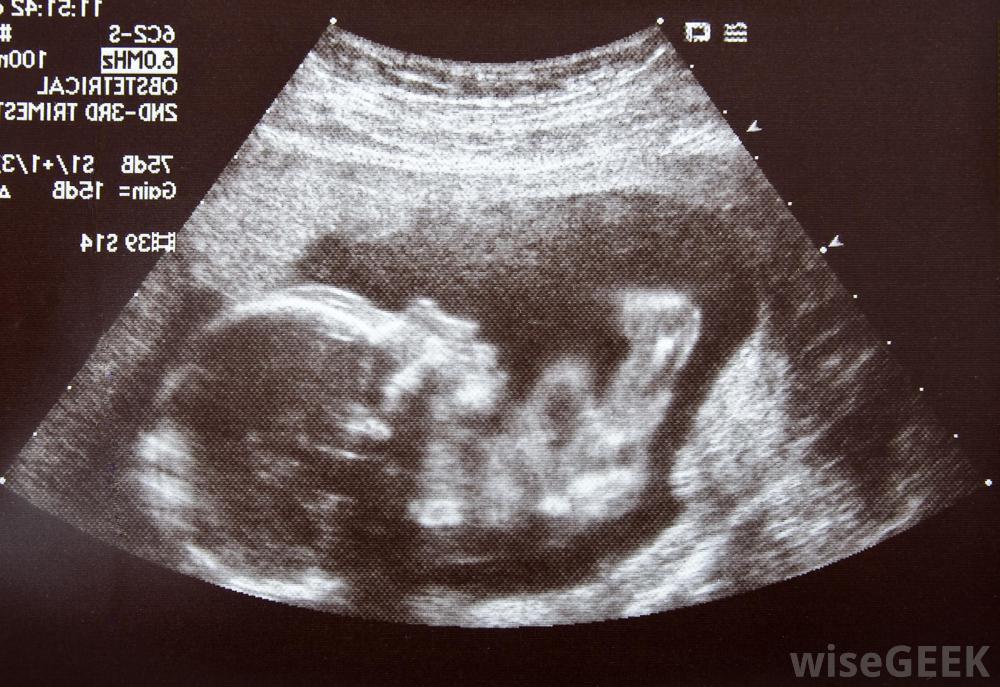

在懷孕的前三個月,孕婦的身體會發生許多變化,通常是由妊娠激素如雌激素和孕激素引起的。這些激素的激增通常被認為是導致各種妊娠癥狀和婦女可能感到的早期不適的原因。這一時期也會給發育中的嬰兒帶來許多變化和快速生長對于大多數女性來說,晨吐開始于懷孕的前4到6周,并在懷孕的前三個月結束。許多孕婦沒有知道她們排卵和受孕的確切日期。因此,懷孕的前三個月,即前12周,通常被認為是從婦女最后一次月經的那一天開始的。實際上,這可能是卵子受精前兩周或兩周以上的時間。一般來說,在受精前的這段時間內,人體內沒有發生與妊娠有關的特定變化。超聲波可以跟蹤胎兒在子宮內的發育過程一旦卵子受精,它會促使女性的身體產生高于正常水平的激素,包括雌激素和孕酮,這些激素幫助身體做好準備,支持嬰兒的成長例如,它們在幫助保持子宮內膜的厚度以保護發育中的胚胎以及胎盤的發育中發揮作用,這是胚胎氧氣和營養的主要來源。由于雌激素等激素水平的增加,在懷孕的前三個月會發生變化懷孕前三個月妊娠激素引起的女性身體的其他變化通常包括子宮和乳房的生長、血液流量的增加和消化系統的減慢。這些變化會導致許多常見的不適感,而這些不適通常是在懷孕的前三個月里懷孕的前三個月,如乳汁管開始生長時乳房變軟,子宮增大對膀胱產生壓力時頻繁排尿,消化系統變慢以吸收更多營養時便秘。特別是一種叫做人絨毛膜促性腺激素(hCG)的激素,它通常被認為是最常見的不適:晨吐。這種由hCG引起的惡心的感覺實際上可能在一天中的任何時候發生。每個懷孕期都是獨一無二的懷孕的前三個月也會給發育中的嬰兒帶來很多變化,在懷孕的最初幾個星期里,受精卵會發育成一個小的干細胞球,然后植入子宮內膜干細胞是一種特殊的細胞,可以發育成任何其他類型的人類細胞。在懷孕的第五周左右,這些特殊細胞開始分化并形成熟悉的人體器官系統。此時,受精卵被稱為胚胎通常在胚胎期發育的第一個器官系統是神經系統,包括大腦和脊髓,以及包括心臟和血管在內的循環系統。這些系統通常在懷孕前三個月的第五周開始發育。在第六到第八周,胚胎開始發育頭、臉、眼、臂和腿。大約在第9周,手指、腳趾、肌肉和骨骼通常開始發育。大約10周時,生殖器通常開始發育。一般來說,懷孕前三個月的最后兩個星期標志著胎兒階段的開始。在這期間,胎兒開始快速生長。在第10周結束時,大多數胎兒只有大約1英寸(2.54厘米)長,但到懷孕前三個月結束時,他們的尺寸通常已經增加了三倍,達到約3英寸(7.62厘米)這種快速生長通常持續到懷孕的第二個月和第三個月,直到嬰兒出生。